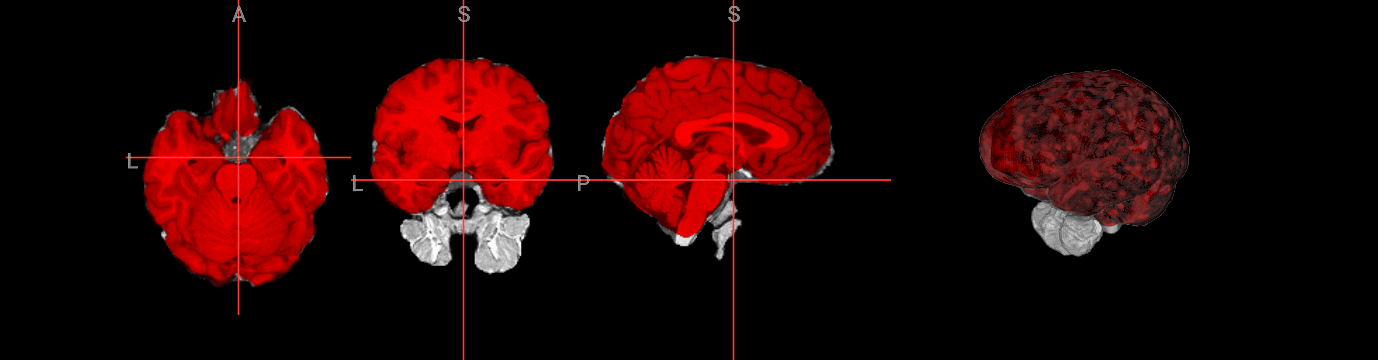

Brain extraction is a fundamental preprocessing step in neuroimaging analysis, particularly critical for structural image segmentation where precision matters most. While BET is straightforward to use, achieving optimal results often requires understanding how to fine-tune parameters for challenging datasets. This interactive version covers the core BET fundamentals, including parameter adjustment techniques for difficult images, and troubleshooting approaches for problematic cases. The hands-on format allows you to experiment with different settings and immediately see their effects on brain extraction quality.